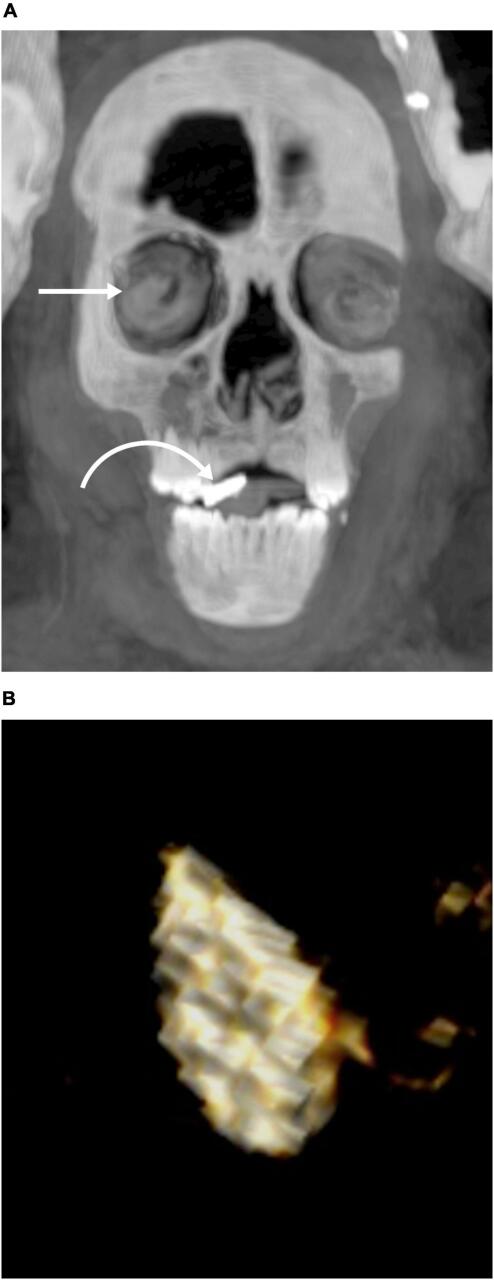

Ученые провели компьютерную томографию, чтобы изучить останки "золотого мальчика" - древнеегипетского подростка 14-15 лет высокого социально-экономического статуса, жившего во времена царства Птолемеев. Выяснилось, что его мумифицировали с 49 амулетами 21 типа, которые, согласно верованиям, способствовали его телесному воскрешению в загробном мире, а его тело было украшено гирляндой из папоротников, что также имело большое ритуальное значение.

У умершего были здоровые зубы и кости без признаков плохого питания или болезней. Среди амулетов были обнаружены Уджат или глаз Гора, скарабей, амулет, символизирующий горизонт (Ахет), плаценты, узел Исиды и многие другие. В рот помещали амулет с золотым языком, чтобы умерший мог говорить в загробной жизни. Многие были сделаны из металла, возможно, золота, а некоторые - из полудрагоценных камней, обожженной глины и фаянса.

Мумия была помещена в два гроба: внешний гроб, украшенный греческим текстом, и внутренний деревянный саркофаг. На голову была надета позолоченная маска, на груди располагалась картонажная пластина, закрывавшая переднюю часть туловища, а на ногах - погребальные сандалии. Не считая сердца, которое осталось в груди, все внутренности были удалены через разрез, а мозг удален через нос и заменен смолой.